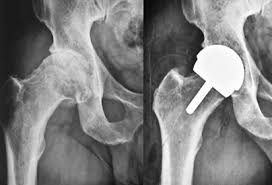

Patients with severe hip pain, arthritis, fractures, or joint degeneration meeting the scheme’s criteria can access free surgery. Eligibility is confirmed after a medical assessment at Varunam Hospital, Chandrapur.

Yes, the scheme covers hospital charges, surgical fees, implants, and postoperative care, minimizing financial burden for patients in Chandrapur.